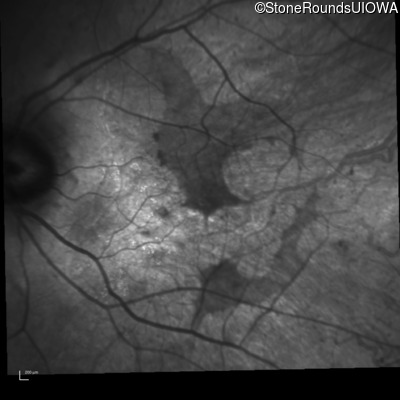

Infrared Fundus Photograph - Right - 20/50 sc

Exemplar